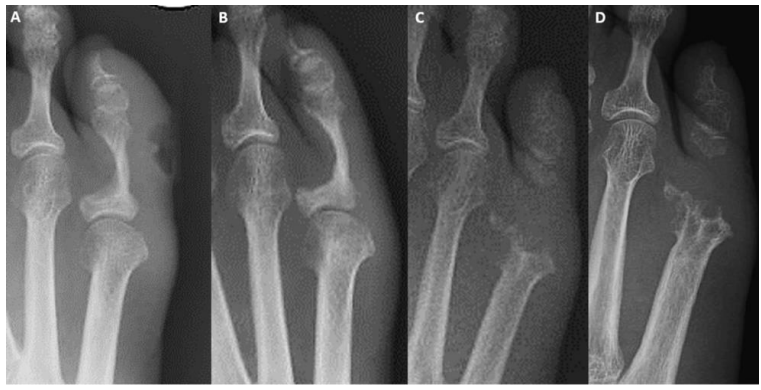

Figure 1: Radiographs

Selection of radiographs demonstrating gradual and complete destruction of the proximal phalanx and fifth metatarsal head. Initial presentation (a), 15 months later (b), 26 months later (c), 30 months after initial presentation (d).

Our case is the first to report an IO-EIC in a metatarsal and a suspected “inside out” mode of cyst rupture with violation of the skin. The hair from the cyst penetrated not only the deep prearticular tissues, but the skin away from the suspected ulcer, creating a secondary nidus for infection. Our patient had no prior history of trauma or surgery of the affected toe. She was an intravenous drug user but had never injected at or adjacent to the foot. This history of substance abuse, her ten-pack years of smoking and the above clinical features pointed towards an “outside-in” loss of skin integrity and infection as the primary diagnosis, which initially favored non-surgical treatment of a suspected superficial infection. Her normal inflammatory markers at presentation and lack of pyrexia were attributed to the excessive use of antibiotics and an EIC was not suspected until dysplastic hair was found intraoperatively. Initial radiographs were also misleading in that the changes were more pronounced at the proximal phalanx [figure 1]. These included a well demarcated zone of destruction and sclerosis, likely resulting from the extraosseous pressure of a ruptured metatarsal cyst, a tracking infection and/or an abscess.